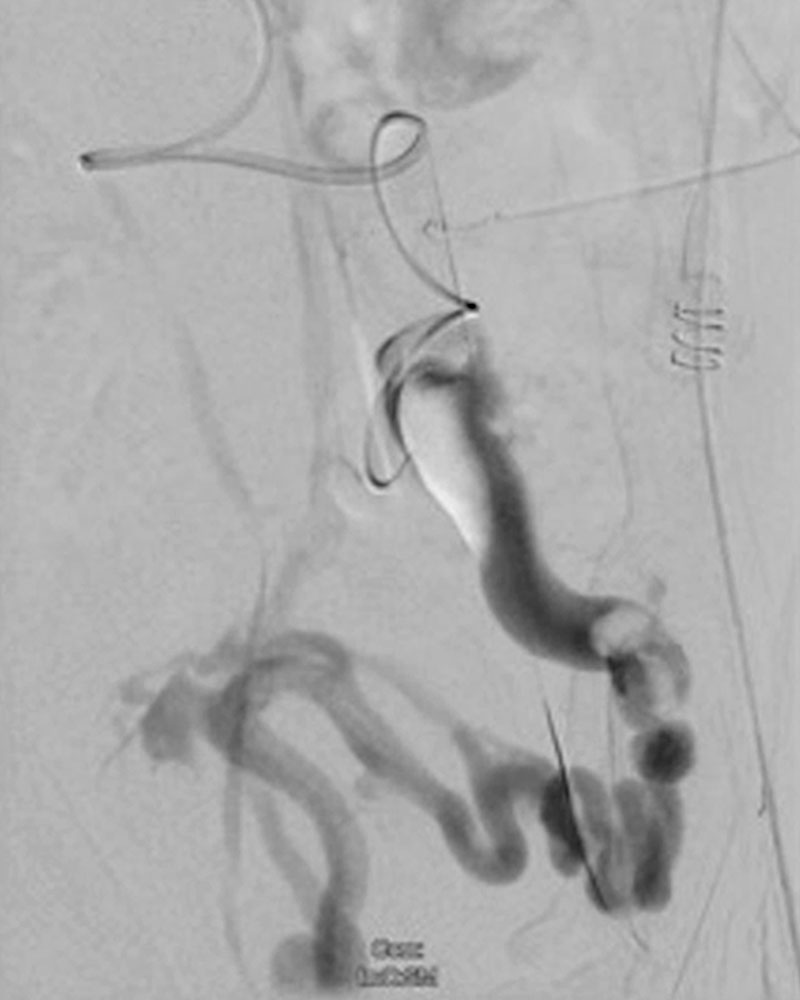

Phlebography has been almost entirely replaced by ultrasound, CT or MR phlebography for the diagnosis of phlebothrombosis and is no longer indicated. Phlebography nowadays is mostly performed as varicography in the direct puncture technique in the context of interventional procedures. In this situation the thrombus is visualized as an intraluminal contrast medium filling defect in the vein.

Invasive measures today often include minimally invasive, catheter-guided mechanical or pharmacomechanical procedures. In these procedures, the acute thrombus is dissolved by mechanical or pharmacomechanical catheter therapy in a minimally invasive manner. Chronic occlusion, especially in the iliofemoral location descending from an iliac vein, can also be reopened minimally invasively, and stents are usually implanted. Open surgical therapy of acute thrombosis is very rarely indicated today, primarily in cases of iliofemoral thrombosis with occlusion of the pelvic venous circulation, and may be combined with creation of an arteriovenous fistula in the groin to keep the reopened vein open. However, appropriate measures should always be performed at a center.

Specific therapeutic measures for phlebothrombosis in patients with venous malformations (VM) should be performed if the vascular malformation is the cause of the thrombosis. This is usually the case in large venous malformations that have one or more communicating veins from the VM into the draining venous system (also called “drainage vein”), and in VM patients with large, dysplastic, dilated veins that communicate with the conducting deep venous system (e.g., marginal veins in patients with Klippel-Trénaunay syndrome) or an embryonically persistent sciatic vein in the thigh. In these cases, occlusion of these communicating veins by minimally invasive or open surgical measures should be performed as causal therapy to avoid thromboembolism with pulmonary embolism in the long run.